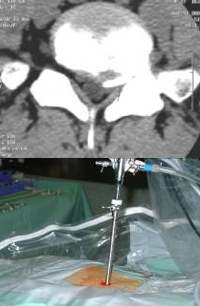

• 行腰椎CT和MR检查,观察腰椎问盘突出部位和程度、是否伴有腰椎管狭窄和椎间盘钙化,确定手术方式、工作通道的置入位置与方向。

体表定位(用克式针标记进针路线)

椎间盘突出在L2-L3和L3-L4水平,选择在旁开中线10 cm进入。椎间盘突出在L4-L5和L5-S1水平,选择在旁开中线12-14 cm进入。实际的旁开距离还需要依病人的身体大小和肥胖程度作适当调整。肥胖、椎间孔狭小、小关节面假性关节病的病人旁开的距离要大一些。对向下掉的髓核,进入点要偏向头侧和外侧。

体表定位(C型臂下影像)

放置导丝(扩张软组织)用锋利的小手术刀在进针点皮肤切开一个大约8 mm的切口。沿着导丝向小关节方向插入导杆。在导杆外沿着导杆逐级放套管向外扩张软组织。

扩椎间孔骨钻套在套管的外边。沿着套管放置骨钻,去掉小关节远端增生的骨质,扩大椎间孔。

使用骨钻时,用C型臂从前后和侧面确定器械和骨钻顶端的位置。骨钻的最前端不能超过中线,以避免刺激或损伤神经。

放置工作套管(工作通道)独特设计的套管顶端可以保护神经根免遭损伤

用C型臂确定工作套管放置的位置。正确的位置应该是放在神经根下方,椎间盘水平,顶端正好在中线,开口朝向突出的髓核。